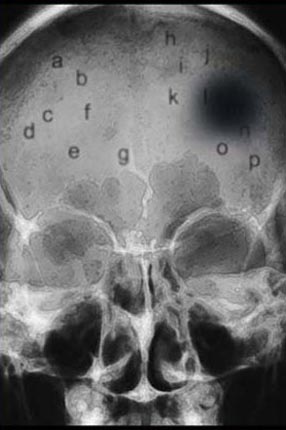

In this series I concentrated on Lenticular prints (hologram-like images generated on the computer). Body/Self 8 is a Mammogram, Body/Self 5, 6, 10 and Crisis are drawings that were converted to lenticular prints. The Crisis image was produced in reaction to my mother's stroke.